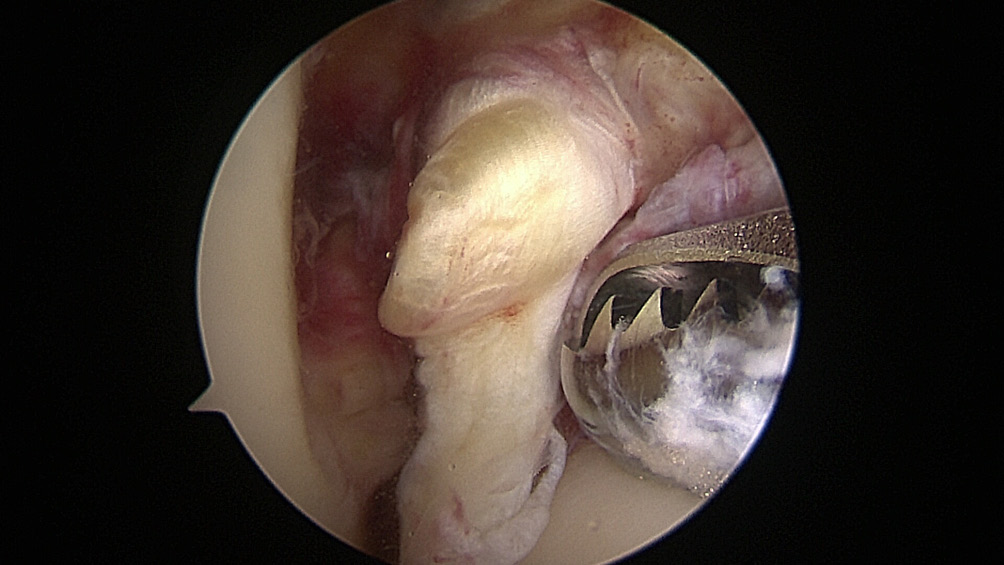

All the patients were operated on by the same team, using the same surgical technique and Neoligaments (Neoligaments) (Figure 1) or FiberTape (Biomet) (Figure 2) graft. It was fixed using Endobutton (Smith-Nephew, Watford, UK) on the femur and the interference screw, ComposiTCP30 (Biomet), on the tibia. It was prepared using the “outside-in” technique with the aimer device (Figure 3, Figure 4, Figure 5, Figure 6, Figure 7, Figure 8).